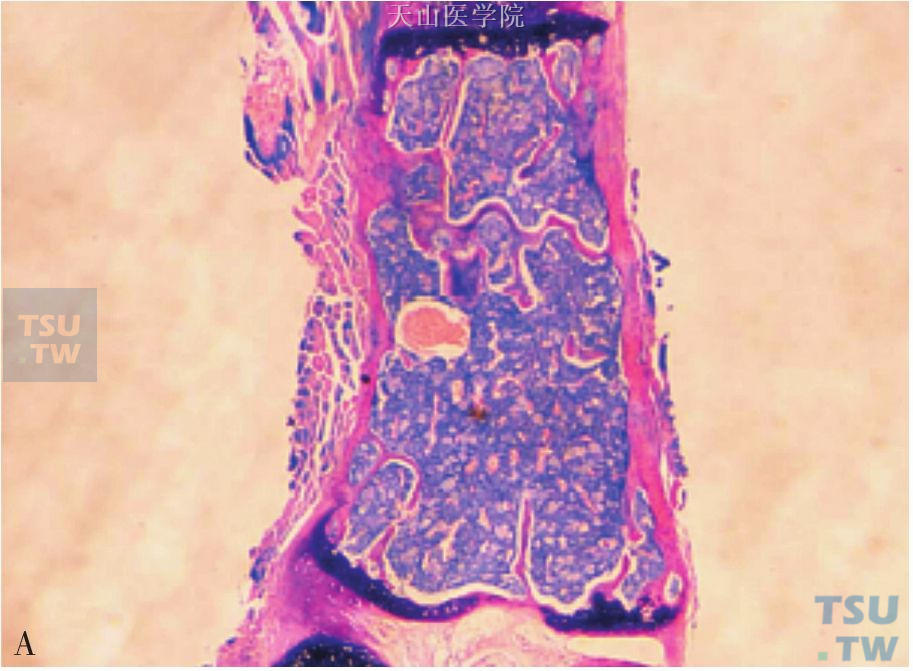

病例与思考患者,男性,58岁,因上腹痛半年,加重伴腹胀半个月入院。查体:贫血貌,左锁骨上淋巴结肿大,肝脏肋下3cm,剑突下5cm,质地韧,双下肢轻度水肿,余查体未见异常。KPS评分80分。入院后C